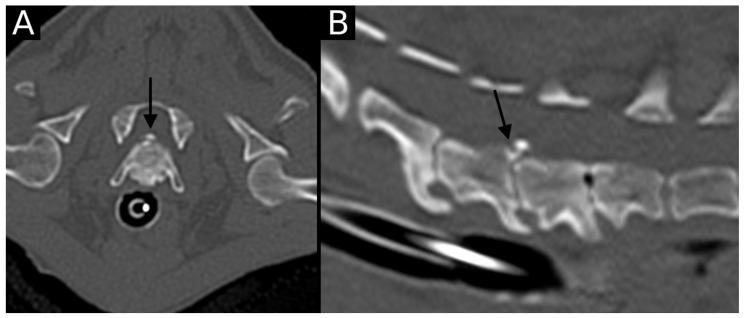

Spinal degenerative changes can predispose back pain and neurological deficits in dogs. In humans and veterinary patients, the endplate junction has been proposed as an alternative site of failure in addition to damage of the annulus fibrosus, leading to intervertebral disc herniation. Some alterations lead to contour abnormalities with or without regional mineralizations and can be classified as Endplate Junction Failure (EPJF), osteochondrosis (with or without fragmentation), or spondylarthritis. The objective of this retrospective study was to describe the prevalence of endplate junction alterations (EPJA) on CT in dogs at the cervicothoracic junction and classify alterations based on recent presumed EPJF grading. Computed tomographic scans of 315 dogs that included the cervicothoracic (C6-T2) spine for a variety of reasons obtained between January 2020 and December 2022 were assessed for the presence of alterations, location and type. Other spinal abnormalities were also described. A total of 945 intervertebral disc spaces were evaluated, and EPJA were found in 11 intervertebral disc spaces (1.16%). C6-C7 and C7-T1 intervertebral disc spaces were equally affected (five cases each), with only one case affecting T1-T2. In conclusion, cervicothoracic endplate alterations were anecdotically observed on CT in a population of dogs.

脊柱退行性变可使犬易患背痛和神经功能缺损。在人类和兽医患者中,除了纤维环损伤导致椎间盘突出外,终板连接已被认为是另一个可能的失效部位。一些改变会导致伴有或不伴有局部矿化的轮廓异常,可分为终板连接失效(EPJF)、骨软骨病(有或无碎裂)或脊椎关节炎。这项回顾性研究的目的是描述犬在颈胸交界处CT上终板连接改变(EPJA)的患病率,并根据最近假定的EPJF分级对改变进行分类。对2020年1月至2022年12月期间因各种原因获取的315只犬的颈胸段(C6-T2)脊柱的计算机断层扫描进行评估,以确定是否存在改变、位置和类型。还描述了其他脊柱异常情况。总共评估了945个椎间盘间隙,在11个椎间盘间隙中发现了EPJA(1.16%)。C6-C7和C7-T1椎间盘间隙受影响程度相同(各有5例),只有1例影响T1-T2。总之,在一组犬中,CT上偶然观察到颈胸段终板改变。